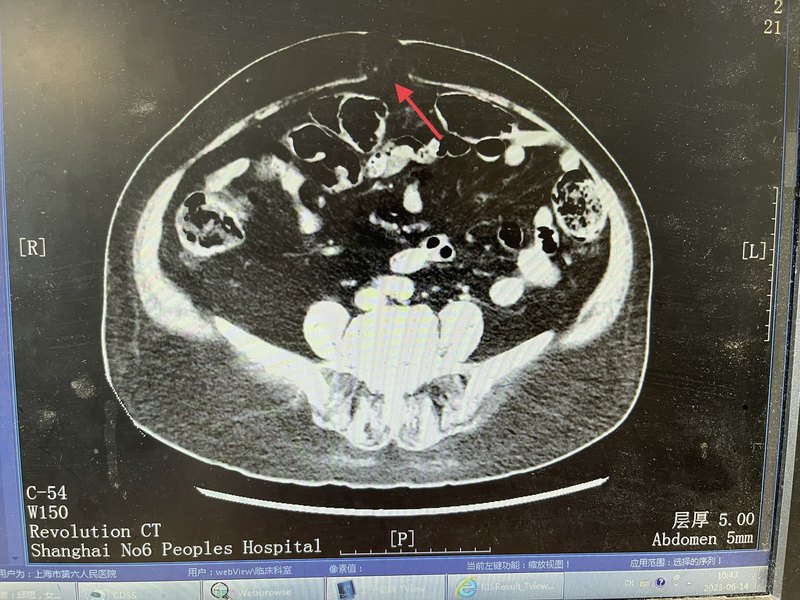

今天的故事從肚臍開始。臍,位于前腹壁上居中的一個結構,是人類在胎兒時期與母親連接的唯一門戶(臍帶,或稱臍索),在出生后臍索會“瓜熟蒂落“,脫落后留下的疤痕遺跡就是你腹壁上的臍。換句話說,人類有“臍”結構,這是胎生的證明,說明你有母親,是有媽的孩子!不像孫吾空,是從石頭逢里蹦出來的。所以,從“臍”這個結構的角度來看,無論如何贊美我們母親之偉大,都不為過。(圖胎兒、臍索和胎盤)臍疝在嬰兒中是常見的,在嬰兒中,當嬰兒哭泣時,臍疝可能特別明顯,導致肚臍突起。這是臍疝的典型癥狀。到了兒童時期,臍疝通常在出生后的頭兩年隨著生長發(fā)育自行閉合,盡管有些在第五年或更長時間內(nèi)仍然有疝囊,有開放的潛能,但不能為手術指征。成年期出現(xiàn)的臍疝才更可能需要手術治療。這是為什么?這里面可能又藏著好些個值得好好研究的問題?;氐浇裉斓闹黝},我們講的是外科歷史和人文,講的英國的歷史。打開外科學的歷史,里面腥風血雨,特別是外科剛剛開始的時候,很黑暗,很多事情讓當今的世人感覺不可思議。這里我們簡要回顧一下英國的歷史,說宗教對英國還是非常重要的。??在15世紀到16世紀歐洲各國之間混戰(zhàn),有人說歐洲的前三場戰(zhàn)爭,是法國路易十四建立了霸權,于1680年開始,成為歐洲至高無上的霸主。但接下來的后兩場大戰(zhàn),歐洲各國團結起來,抗擊路易十四霸權。與路易十四對陣荷蘭、英國、西班牙、羅馬帝國等國的組成了反法大同盟軍,最終將法國被打到破產(chǎn)。西班牙國王位繼承戰(zhàn)爭,爆發(fā)于1701年,一直打到1714年。反法大同盟軍的統(tǒng)帥成了英國威廉三世,英格蘭國王、蘇格蘭國王、愛爾蘭國王等在英國威廉三世的率領下。繼續(xù)戰(zhàn)爭。威廉三世在位末期,身體狀況不佳,(威廉是基督教徒,但此時皇親國戚與歐洲各國聯(lián)姻大多是天主教徒)1701年,英國政府為避免天主教徒繼位為王,頒布了《王位繼承法(1701版)》,規(guī)定,天主教徒不得繼承英國王位,因此,格奧格的母親蘇菲婭,作為基督教,成為英國王位繼承人。英國女王安妮駕崩無嗣,所以向下,排在今天主人公之一的喬治?(George)之前的,還有五十位血緣關系,但他們都是天主教徒,依據(jù)法律不能繼承英國王位。所以喬治母親蘇菲婭去世后,喬治(George)基督教就是血緣和安妮女王最接近的基督教徒了,這樣理所當然,安妮女王去世,喬治得以繼承英國王位,稱喬治一世(George?I)。這里要說,喬治一世他是以德語為母語的英國君主,換言之他根本不懂英語,也不會說,聽不懂,也不看英文,于是,他下令以輝格黨領袖斡博爾爵士為內(nèi)閣首相,主持各種事務,他作為國王則不出席內(nèi)閣會議了。從此英國開創(chuàng)了先例,國王不再出席內(nèi)閣會議,改由一名國王的親信大臣(首相)參加,這便成了英國首相制的開端。英國的漢諾威朝(1714到1901)延續(xù)近兩百年。漢諾威朝是英國歷史上最偉大的朝代,漢諾威朝時期,建立了大英帝國即英格蘭、蘇格蘭、愛爾蘭統(tǒng)一。漢諾威朝,六代帝王。王朝前期,就稱為喬治王時代,有喬治一世、喬治二世、喬治三世、喬治四世,連續(xù)五代。其實,喬治一世、喬治二世其實都是德國人,都不會說英語,以后的各王,才是在英國出生長大的英國人。今天故事的開頭要從1683年始,英國老國王喬治一世和王后索菲亞在這一年兩人終于生出了他們的獨生子取名GeorgeAugustus,,但他的出生地也不在英國,而是生于德國漢諾威(1683年10月30日)。這年是中國的農(nóng)歷癸亥年(豬年)已經(jīng)是清代康熙二十二年),直到1705年,他為了繼承王位,才入籍英國,1705年,他與勃蘭登堡的卡羅琳公主(Caroline)結婚?;楹笏麄冇兴膫€兒子和五個女兒,但多數(shù)都英年早逝。喬治二世頭像的英鎊喬治二世畫像故事的主人公是喬治二世的夫人,卡洛琳(Caroline),卡洛琳出身貴族。當1705年喬治二世與卡洛琳到達時英國時,這個原在德國家庭,發(fā)現(xiàn)他們在英國生活的氛圍才非常時髦。當時有階層的人多帶假發(fā),人們將這個時代命名為“格魯吉亞時代”。剛入英國,王室成員間互相用法語交談,在公共場合用帶有濃重德國口音、他們聽不懂的英語。英國的兩個喬治王,治理國家都是一般般,是出了名的“推遲綜合癥患者”,對他們的評價都是粗野、遲鈍、喜怒無常。卡洛琳而當時的國王完與公主卡洛琳則完全相反。她有趣、迷人、機智、美麗,卡洛琳還斡旋于政治,對于喬治二世的王位繼承非常重要。成為王后和她的侍女們成為英國王室魅力和風格的頂點。當時上流社會流行曼圖亞裙,曼圖亞裙這是一種奇形怪狀的裙子,兩側臀部有巨大的延伸部分,由鯨魚須加強筋作為支撐的,它的寬度如此之大,以至于女士們在穿過敞開的門時必須側著身(下圖所示)。這主要是為了顯示她們的腰很細。她們還會在頭上戴一個很高的帽子,在脖子和臉上涂上一層很厚的有毒鉛顏料,在嘴角上方畫上一個黑色的美人痣。然后,她們會被塞進由兩個走卒扛著的只能容納一個人的轎子里——連同假發(fā)、衣服等等,她們在倫敦的各個舞會和社交舞臺上跑來跑去。1727年夏天,老喬治一世在前往Osnabrück的馬車上死于中風。同時,新國王喬治二世和他的妻子卡洛琳王后等了13年才登上王位。在13年的奢侈和無所事事中,曾經(jīng)那么美麗的卡洛琳已經(jīng)變得肥胖得無可救藥。轎子根本坐不上了,甚至穿裙子也困難。雖然她的真實尺寸從未在肖像畫中出現(xiàn)過,她巨大的胸,名聲最終比她在現(xiàn)實中更大,但當卡洛琳最終成為王后時,她是如此巨大的王后,據(jù)計截她的太胖了以至于要幾個仆人的幫助她在床上翻身。而她的丈夫,國王喬治二世,卻找了個情婦(就是妻子的侍女首領)。在那個年代,王后卡洛琳可能并不為自己的暴飲暴食或由此而橫向發(fā)展的身材感到羞恥。甚至普通市民可以在周日買票觀看這對皇室夫婦用餐。人們可以看到女王,她的巨大肥胖的身體,自顧自的吃東西。她還有一個只有她丈夫知道的秘密。由于超重和多次懷孕,在生下小女兒露易絲公主后,她的腹部中部開始隆起,即臍疝。她巧妙地把這個凸起藏在衣服下面。這是一個臍疝,最終增長到一個“巨大的尺寸”。沒有人知道它到底有多大,但是,特別是對于超重的人來說,臍疝可以是巨大的,比如像西瓜那么大。臍疝病人,當腸子或內(nèi)臟通過臍部的缺損在腹壁肌肉中從腹腔中突出時,臍疝的表現(xiàn)就明顯。臍是在出生后留下的,通常不到半厘米,臍環(huán)也小到足以承受腹部的壓力。然而,如果腹部內(nèi)容物長時間膨脹,例如由于過多的脂肪組織或多次懷孕,臍環(huán)強度會減弱,被拉伸過大時腹腔的內(nèi)容物可以通過擴大的開口被推入;隨著時間的推移,腹內(nèi)內(nèi)容物可以推出的越來越多。如果臍口繼續(xù)變寬,突出的腸子在疝中保留足夠的空間不被卡壓。隆起只會造成不方便的觀感不佳,但當腹部壓力突然上升時,比如咳嗽、打噴嚏、大笑或緊張時,疝環(huán)卡壓住疝內(nèi)容物才會感到疼痛。若此時患者仰臥時,因重力影響作用會降低疝內(nèi)的壓力,使疝內(nèi)容物腸子回到腹部原來的位置,腫脹消失,直至患者再次站起來。這種自行或位體性的還納復位對病人的生活影響不大。但如果有更多的腹部組織進入疝囊。癥狀會加重,直到患者仰臥時腫塊也不會消失的程度,換言之,臍疝不能再復位了,疝的病程走入了死胡同,如果更多的腹部內(nèi)容物被迫進入疝,它會變得嵌頓,會引起突然劇烈的疼痛和嘔吐。此外,如果不采取措施減少臍口的壓力,疝囊中的組織就會壞死、絞窄。絞窄性臍疝的結果取決于被絞窄的是哪種組織,哪位外科醫(yī)生處理這種問題,尤其是他在什么時候這樣做。1737年的夏天,王后卡洛琳的腹部曾有兩次劇烈疼痛,但兩次都自行好轉(zhuǎn)并消失了。秋天后,11月9日星期三上午,她再次經(jīng)歷了極度的疼痛,這些情況在約翰·赫維勛爵、溫斯·張伯倫,皇室夫婦的私人朋友的回憶錄中有詳細的記錄。王后的疼痛劇烈,難以忍受,并伴有嘔吐。然而,那天晚上她還是堅持要像往常一樣出現(xiàn)在客廳里。晚上,她繼續(xù)干嘔,甚至不能靜靜地躺著,仆人給她喝的薄荷水和草藥苦味劑癥狀沒有減輕,腹痛也沒有消停。最后沒有辦法,傳喚了將英國皇家外科,前來出診的醫(yī)生是約翰·蘭比(RANBY,JOHN(1703–1773)皇家外科協(xié)會的主任,他采取了激進的措施:醫(yī)囑是給王后卡洛琳喝威士忌,并立即給她放血12盎司(約等于351.2毫升)。第二天對外科醫(yī)生蘭比(Ranby)來說是忙碌的一天。他開始給王后放更多的血,因為王后她仍然沒有感覺好一點。記載此時他還得照顧卡洛琳的女兒卡洛琳,因為女兒在母親王后的床邊哭了很久,哭到流了鼻血。蘭比對如何治療這位痛苦的年輕女士胸有成竹。他也給王后的女兒也放了血兩次。與此同時,各種各樣的醫(yī)生對王后進行各種各樣的治療。他們讓王后將她腿上一整出水泡,讓她喝長生不老藥,又給王后灌腸,盡管沒有人知道她到底出了什么問題。這群醫(yī)生們的診斷是“胃痛風”。有治療組的其中一名醫(yī)生因為說王后可能無法康復,而被國王喬治二世扇了一耳光。周五早上,王后的下面又排血了便,但腹痛還在繼續(xù),她把吃的喝的都吐了出來。直到第二天,國王喬治二世感覺再也掩飾不住了,才向醫(yī)生們說出了王后的秘密。他說:我違背她意愿,并告訴蘭比醫(yī)生,說,王后她隱瞞了超過13年的臍疝。直到那時——她生病的第四天——病人才被醫(yī)生檢查出問題所在,蘭比感覺到她腹部的腫脹,立即又叫來了兩位外科醫(yī)生同行,一位叫布西耶。有經(jīng)驗的80多歲老宮廷外科醫(yī)生,和一位年輕的城市外科醫(yī)生約翰·希普頓。在這三個醫(yī)生照顧女王時,喬治二世開始接手管理妻子的財產(chǎn),情況發(fā)展致此,終于得到了皇室重視。醫(yī)生組里的老布西耶醫(yī)生建議做一個大范圍的手術,在疝深處切開臍部開口,這樣被絞窄的腸子就能被推回腹部。這表明這位上了年紀的外科醫(yī)生仍然擁有敏銳的外科思維,但這位老醫(yī)生,在當時的考量顯然走在了那個時代的前面,治療組里蘭比醫(yī)生反對這個建議,而希普頓醫(yī)生同意蘭比醫(yī)生的建議,所以結論是觀察等待(wachtingandwaiting)。然而,隨著時間的推移,病人的疼痛加劇了。到了傍晚時分,蘭比醫(yī)生提出了一個難以理解,妥協(xié)方案,即在疝的上方開一個切口,切口不能深過腹腔。晚6點左右,三位英國1737年的專家們圍著王后的床,在燭光下勇敢的為她做起了手術。王后習慣于睡在五張床墊上。這對三位外科醫(yī)生來說,一定是一項非常繁重的工作,他們不僅要在那堆床墊上彎下腰來,還要在病人的身體上彎下腰來。蘭比醫(yī)生的夾克被汗水濕透了。按原版書籍記載的那樣:就像三個外科醫(yī)生像在解剖室里處理一具尸體上一樣,他們切開隆起的肚臍的皮膚,(那個時間還沒有消毒和麻醉的觀念)試圖把現(xiàn)在可見的東西推回到女王的腹部。這一定是王后一生中最痛苦的時刻,沒有麻醉、沒有肌松劑醫(yī)生們?nèi)绾文茏龅??他們的努力都白費了。手術后接下來的更悲慘:這個國家至高無尚的,最著名的王后現(xiàn)在不僅有一個絞窄的臍疝,而且還有一個巨大的傷口。沒有無菌和抗生素的年代感染是無法避免的。盡管做手術的三位外科醫(yī)生很擔心——而且有很好的理由這種可怕的情況最終會如何結束,但他們忽略了王后的病情好轉(zhuǎn)的明顯跡象。據(jù)記載:如果腸子真的被嵌頓壞死了,卡洛琳肯定不能再活過那漫長的五天。死亡的腸壁會讓壞死細胞的有毒腸內(nèi)容物、消化液在幾個小時內(nèi)進入腹腔,而后吸收入血液。那會導致災難性的機體內(nèi)生物化學連鎖反應和炎癥風暴,會立刻破壞她體內(nèi)的所有系統(tǒng)。她會在兩天內(nèi)死去。但在11月13日的星期天,術后她仍然很有活力,非常清醒,對她床邊的人做出了回應。可能是切開了腹壁,腹壁上嵌頓被減壓了,當時嵌頓壞死的是碩大而肥厚的大網(wǎng)膜組織。不一定是小腸,兩者不同之處在于,盡管被嵌頓卡死的大網(wǎng)膜很痛苦,但卻沒有那么危險,因為與將要死亡腐爛的腸道相比,卡死的脂肪細胞液化后使受害者的疾病減輕了。周日,也就是手術后的第二天,外科醫(yī)生對疼痛的傷口進行了處理。因為他們現(xiàn)在白天看得比前一天晚上在燭光下看得更清楚了,他們突然注意到疝深處的受損脂肪組織。在那些日子里,傷口上的任何痛苦通常被認為是病人很快會死于壞疽的確切信號。因此,盡管王后殿下并不比前一天感覺更糟,也沒有其他跡象表明她即將死亡,但當場的三位外科醫(yī)生還是經(jīng)驗不夠,認為她只能活幾個小時了。國王喬治二世被叫去向她告別。國王傷心欲絕。他承諾永遠忠于他心愛的妻子,即使在她死后。而王后殿下卻勸告他再婚。國王喬治二世抽泣著,說了一句具有歷史意義的話:“Non,j'auraidesmaftresses”(不,我還擁有情婦!)王后卡洛琳大呼:“我的天哪,那又有什么區(qū)別!”。之后,外科醫(yī)生們又開始緊張的工作了。當清理傷口他們切除壞死組織時,他們再次沒有注意到傷口沒有排泄物流出的好跡象,這意味著他們上次手術切除的不是腸道。王后卡洛琳的好友,勛爵張伯倫·赫維對外科醫(yī)生處理病人及其親人情緒的冷漠態(tài)度越來越感到不安。就在幾個小時前,外科醫(yī)生們還宣布王后命不久矣,而事實上事情并沒有發(fā)生,那三個醫(yī)生表現(xiàn)得好像什么事也沒有發(fā)生。王后殿下臍部傷口痛苦對她的生命好像沒有直接影響,在接下來的幾天里,王后殿下又接見了政府首相和大主教。然而,她越來越虛弱。她仍然咽不下任何食物,還不斷地嘔吐。外科醫(yī)生每天都在給她做手術,處理傷口,切除壞死組織,后來又把手指伸進去,用探針探測,當然,所有這些都不需要任何形式的麻醉。在一次手術中,年邁的布西耶把蠟燭舉得離頭太近,導致醫(yī)生的假發(fā)起火。英國的報紙公布了這些一個個可怕的細節(jié),導致后來王后卡洛琳的案件被公開辯論,用Hervey的話說,“就好像她在(皇宮)里面被解剖了一樣”。直到11月17日(星期四),情況才真正變得更糟,當時她的腸子在換藥處理時肯定被戳破了。嘔吐加劇,傷口突然開始流出大量糞便樣物。當糞便從王后的肚子里噴涌而出,浸透了王后殿下的床單,流趟在她臥室的地板上時,東西大多,沒有辦法,王后殿下寢室的窗戶因為惡臭被打開了。然而,依然堅強的王后殿下又堅持了漫長的三天,于1737年11月20日星期天晚上10點卡洛琳王后殿下在骯臟、最悲慘的環(huán)境中死去。享年54歲。無論如何,這位卡洛琳王后殿下給英國的后人上了深刻的一課,在那個年代外科手術弊大于利的時代,唯一正確的治療方法是不做手術,觀察和等待”(wachtingandwaiting),所以,wachtingandwaiting的理念被刻入了英國外科醫(yī)生的骨子里,和基因里,若不信,你看看《歐洲的疝指南》里面一定會有“wachtingandwaiting”。除了王后之死,14年后,175I年12月19日,歷史在丹麥重演??辶盏呐畠褐宦兑捉z公主,,嫁給了丹麥國王,也成了王后。和她目前一樣,她很肥胖。在她二十七歲的時候,她懷著孕,和她母親一樣出現(xiàn)了嵌頓臍疝。一名外科醫(yī)生再次試圖挽救她,但卻徒勞無功。在和她母親同樣可怕的情況下,她失去了年輕的生命和孩子。外科醫(yī)生盡管在他的職業(yè)生涯開始時遭遇了這樣的慘敗,約翰·蘭比對自己的評價非常高。在1744年他出版的《槍傷治療方法》一書中,描述了自己在英國軍隊中擔任軍醫(yī)的最輝煌時刻。他的英雄事跡之一是對待威廉王子,國王喬治二世和已故女王卡洛琳的小兒子,也被稱為“屠夫”。1743年,在奧地利王位繼承戰(zhàn)爭期間,威廉和他的父親一起在德廷根戰(zhàn)役中對抗法國人。這是英國歷史上最后一次國王親自率領軍隊上戰(zhàn)場。威廉被一顆火槍子彈擊中,子彈直接穿過他的小腿,造成了一個“雞蛋那么大”的傷口。蘭比立刻沖過去幫助流血不止的王子,拔出了他的刀。今天,一個明智的外科醫(yī)生會切開士兵的褲腿來評估傷口,用褲腿做一個結實的加壓繃帶來阻止血液的流動,并盡快把受害者從混亂的戰(zhàn)斗中帶走。但蘭比用他的刀做了別的事。他在倒下的王子手臂上開個口子讓他流血,就在那里,在戰(zhàn)場的中央,火槍子彈在他們耳邊飛舞。他吸了超過半升的血,好像受害者的腿失血還不夠。在戰(zhàn)地醫(yī)院里,他用面包和牛奶包扎傷口,又讓王子流了兩次血。盡管如此,這個年輕人還是活了下來,這讓外科醫(yī)生感到非常榮幸和欣慰。后來,蘭比就不那么幸運了,因為他的治療方式很荒謬。他用放血療法幫羅伯特·沃波爾這個英國首相從尿道取出膀胱結石。在這里,他也想不出更好的辦法,就是再給病人放點血,盡管病人已經(jīng)失血過多以致快要死了。今天的故事告訴各位,作為外科醫(yī)生的你,也許對哲學不興趣,但哲學一定會深深地影響你。哲學教你如何思考方式,如何處理病人符合邏輯性。外科醫(yī)生一定要對其手術的下一步,或之后疾病的發(fā)展和應對的方法心中有數(shù),想清楚才能去做,不能無知而無畏去犯錯。英國媒體對卡洛琳王后之死的討論認為:在外科治療中,“觀察等待”(wachtingandwaiting)也是一種寶貴的工具,無論是在作出診斷還是在改善病人的健康狀況方面。這反映在外科醫(yī)生治療病人時可以采用的三種不同的方法上:1)保守治療(不進行手術干預)、2)預期治療(觀察等待而不進行治療)3)侵入性治療(通過手術干預事件的流程)。你看今天的歐洲疝指南一定寫了對無癥狀的疝可以“觀察和等待”(wachtingandwaiting)。換言之,我們從今天的故事中或多或少可以看到了英國或歐洲的醫(yī)生思維中還留下了300年前歷史的痕跡。